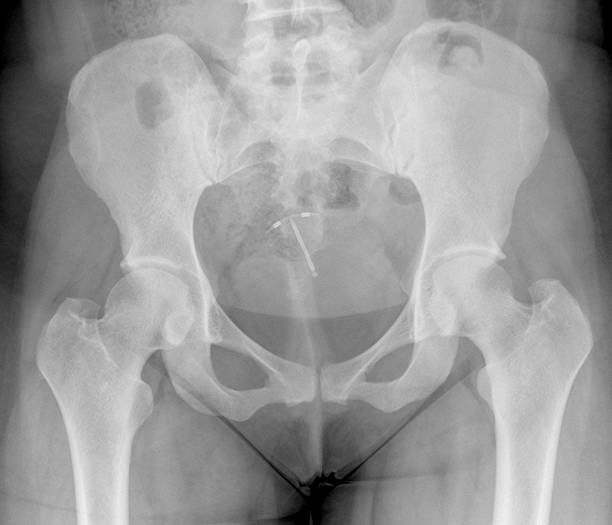

Tijdens een geplande controle, waarbij de artsen nauwlettend de gezondheid van de vrouw in de gaten hielden, besloten zij om een echo uit te voeren om zorgvuldig de positie van het spiraaltje in haar baarmoeder te controleren. Hiermee wilden zij er zeker van zijn dat het spiraaltje correct geplaatst was en geen risico op complicaties met zich meebracht.

Tot grote verbazing verscheen niet alleen het spiraaltje op het scherm, maar ook een klein kloppend hartje, wat Queidy’s emoties deed overweldigen en maakte dit moment onvergetelijk voor haar. Daarom besloten de artsen om de zwangerschap nauwlettend te volgen en ervoor te zorgen dat alles goed zou verlopen.